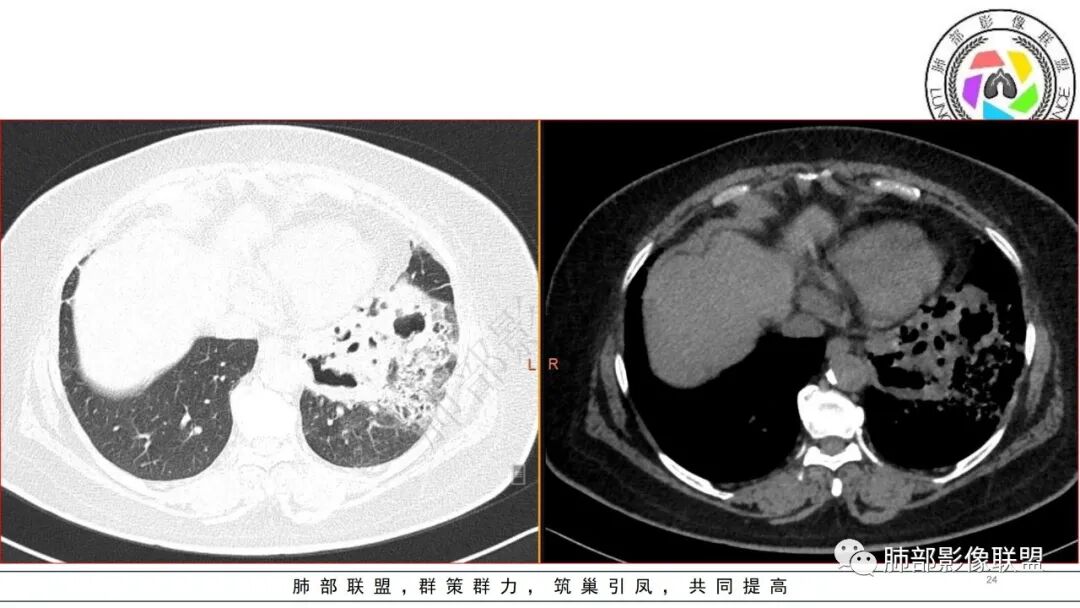

有糖尿病基层,左肺大片状实变影,跨多个叶段,多次治疗复查,实变范围有缩小,部分可见空洞影,考虑肺克

糖尿病,左下肺单侧实变,多次复查可见空洞和液平面,符合坏死性肺炎,白细胞高,遗憾的是不管是前期还是复查都没给PCT值,有手术史,首先考虑肺克,鉴别金葡和大肠埃希菌

糖尿病基础,左下肺感染性病变,进展快,先是左肺大片实变,短时间复查出现空洞,治疗两周周边有吸收好转,空洞壁变薄。金毛结克,我倾向金葡菌。鉴别肺克。

老年患者,糖尿病病史14年,不规律降糖治疗,血糖控制不佳,咳嗽、喘息两天就诊,查血常规白细胞轻度升高,CRP显著升高,首诊CT提示左下基底大片实变,边界不清,周围播散灶,短期复查病灶呈吸收好转趋势,并出现多发空洞,空洞形态不规则,病灶内未见气液平,考虑感染性病变:

2.左肺下叶大范围实性密度影,散乱,边界不清,可见液化空洞,病变肺体积轻度增大。支气管相关(相应支气管闭塞)。

3.五天后及十三天后病灶变化明显,实性密度影吸收缩小,边界趋于清楚,显示多空腔。

4.双侧胸腔未见积液。

5.扫描范围内未见肝脏密度异常影。